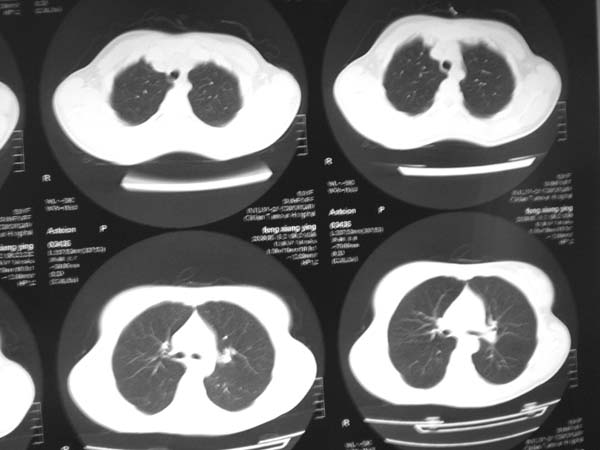

标题: CT13486:F 17Y 咳嗽 咳痰数日请会诊 [打印本页]

标题: CT13486:F 17Y 咳嗽 咳痰数日请会诊

白细胞9600不发烧

考虑右下结核球

右肺下叶结核灶

右下肺背段病灶,考虑结核与炎症鉴别,请进一步检查.

考虑结核球,建议治疗后复查

结核与肿瘤同时考虑

右下肺外基段病灶,考虑炎症,建议治疗后复查,以排外结核

考虑为:右肺下叶外基底段结核球。

结果;痰中找到结核杆菌

痰涂片已找到结核杆菌  将结果告诉大家